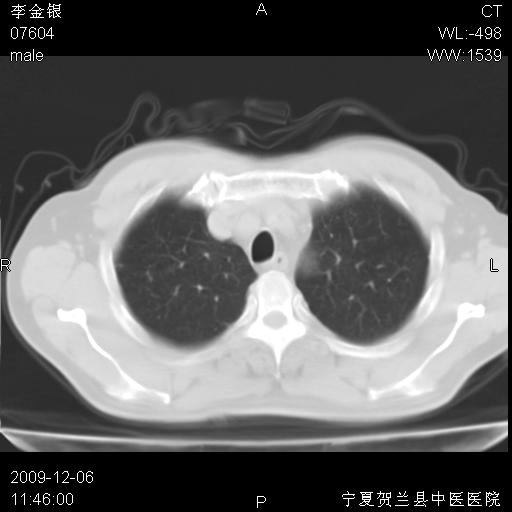

该病人 ,男,62岁,主因咳痰带血两天

考虑右肺中央型占位性病变并阻塞性肺炎.(右肺上叶支气管变窄),建议支纤镜检查.

支持右侧中央型肺癌伴上叶阻塞性炎症.

考虑右肺中心型肺癌伴阻塞性肺炎及右肺门淋巴结转移,建议纤维支气管镜进一步检查。

支气管壁明显增厚 管腔狭窄,腔静脉后多个淋巴肿大,结合年龄病史考虑右肺上叶中央型肺癌并阻塞性肺炎

右肺上叶后段支气管阻塞,右上肺门占位,相应肺段阻塞性肺炎,右肺门有淋巴结肿大。诊断右肺上叶中心型肺癌,阻塞性肺肺炎、右肺门淋巴结转移。

右上叶支气管狭窄,管壁增厚,远端斑片状软组织影,病灶邻近叶间裂,叶间裂无移位。

诊断右肺中央型肺癌。

那个片影应该大部分都是病灶,病灶沿肺段支气管分支生长,后段完全显示不清、闭塞。若为不张应该伴有叶裂的移位,若为炎症应有空气支气管征。